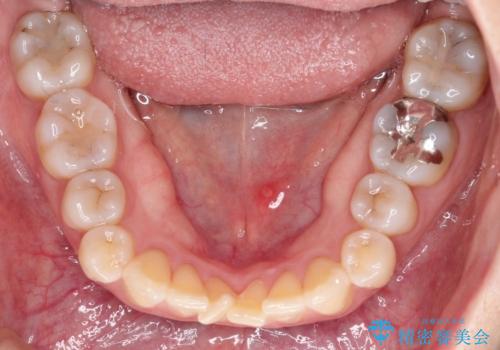

- 前歯の凸凹を主訴に来院されました。

インビザライン にて治療を行い、歯並びが綺麗になったと満足していただきました。

前歯のガタガタの量が多かったため、IPR(歯のサイズを小さくするための処置)を行なって治療しました。